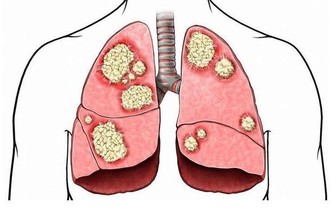

世上有一種癌症,其傳播範圍極廣、惡化程度極快、治療週期極長,一旦患上,無藥可救,只能憑藉病人頑強的意志力去抵抗,你知道是什麼嗎?

「 懶癌」

雖說懶不是病,但有時候,懶起來也要人命!這不是危言聳聽,一旦被“懶”附身,許多疾病,包括癌症都將接踵而至。